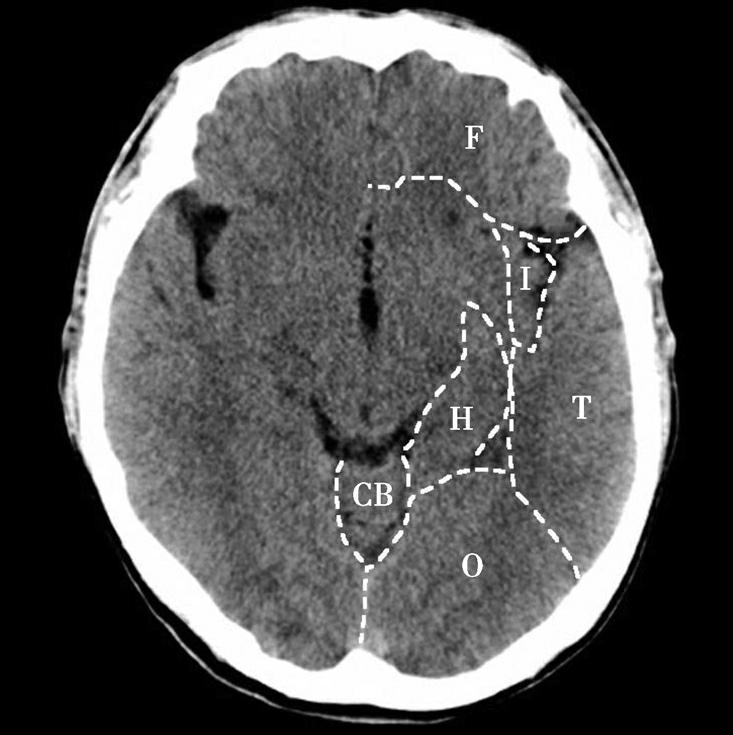

Alberta卒中项目早期CT评分(Alberta stroke program early CT score,ASPECTS)是一种评价急性缺血性卒中患者大脑中动脉供血区早期缺血性改变的简单、可靠、系统化的方法,是常用的脑卒中评定量表之一,可对缺血性病变快速进行半定量评价,有助于判定溶栓效果和远期预后。该评分主要基于CT平扫,具体分区如下(图1-2-76)所示,即选取大脑中动脉供血区2个层面。分区后共10个区域,每个区域记1分。评分时任何区域只要有低密度灶,则扣除该区域得分。正常脑ASPECTS评分为满分(10分),若MCA供血区广泛梗死累及全部区域时,则ASPECTS评分为0分。

图1-2-76 ASPECTS评分脑组织分区

A.在基底节层面(即丘脑和纹状体平面),分为各级分支M 1 、M 2 、M 3 、岛叶(缩写I)、豆状核(缩写L)、尾状核(缩写C)和内囊(缩写IC)后肢等7个区域;B.在基底节以上层面(基底节层面上2cm),包括M 4 、M 5 和M 6 。